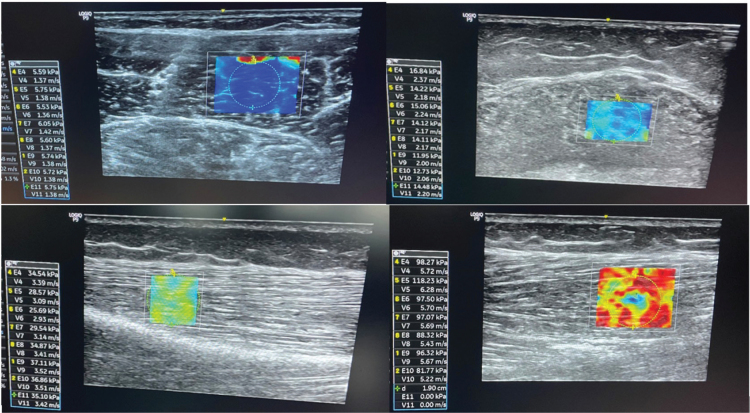

Methods: Botulinum toxin A was administered in relevant calf muscles. Muscle stiffness measurements with shear wave elastography and clinical tests such as spasticity test (Modified Ashworth scale), maximal active and passive dorsiflexion of the ankle, and 10 m walk test were conducted at baseline, after 6 weeks, and after 3 months. Medial gastrocnemius muscle stiffness was measured in both the affected and the unaffected leg. The Goal Attainment Scale was used to evaluate therapy goal achievements.

Results: Significantly reduced muscle stiffness was found at 6 weeks on the affected side, but not at 3 months, and no changes were present on the unaffected side. A moderate positive correlation between muscle stiffness and Goal Attainment Scale score was observed.

Conclusion: Shear wave elastography could evaluate the effect of botulinum toxin A on muscle stiffness in stroke patients over a 3-month period. The correlation between muscle stiffness changes, goal attainment, and function need further longitudinal studies.